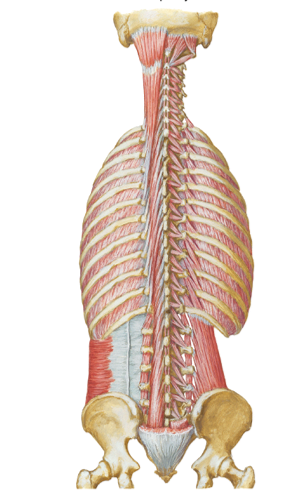

Identify 2 bony landmarks of the posterior thorax

- What is “CVA tenderness”?

Spinous processes of thoracic vertebrae 1 -12

Costovertebral angle (CVA)

- Clinical: “CVA tenderness”: a medical test in which pain is elicited by percussion of the area of the back overlying the kidney...The test is positive in people with an infection around the kidney

name the 2 posterior vertical lines and describe them?

another 2 names for the 1st one?

Posterior median (midspinal or midvertebral) line ...vertical line through spinous processes of vertebrae in mid-saggital plane

Scapular lines...vertical lines that pass through inferior angles of the scapula, line is parallel to posterior median line

posterior median line goes through the inferior angle of the scapula...look for it in the picture and try to picture the bottom of the scapula along the line

what is the auscultation alley?

- Vertical column between thoracic spinous processes and medial border of scapula...want to put your stethoscope here to listen

- if you put the stethoscope on the other side (to the left of the far line) then the scapula will be in the way for you to hear

Identify/describe actions of the following muscles

- Levator costarum (lc)

- where is this one located?

- Serratus posterior superior (SPS)

- Serratus posterior inferior (SPI)

basically, what do the SPS and SPI do?

Levator costarum (lc)...inspiration (elevate the ribs)...the very

small slanted muscles down the posterior spine in the 1st

pic...opposite of "/")

Located external posterior

attach to ribs and Transverse process

Serratus posterior superior (SPS)...inspiration (elevates the

ribs)...on top in second picture

Serratus posterior inferior (SPI)...expiration (depresses the

ribs)...on bottom in second picture

they anchor onto the ribs and spine and either bring it up or down